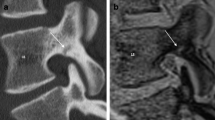

The results of the contingency table analysis comparing disk damage and endplate involvement in MRI and DECT are summarized in Tables 1 and 2. The resulting overall diagnostic accuracy of using DECT to depict disk injury was 0.81 compared with 0.75 for MRI when endplate involvement was the deciding factor. In DECT, SE varied with the grade of disk damage, ranging from 0.80 for grade 1 to 0.85 for grade 2 and 0.98 for grade 3. A collection of different images is shown in Fig. S1. Diagnostic accuracy varied between readers: SE was 0.89 for reader 1, 0.73 for reader 2, and 0.86 for reader 3, and SP was 0.93 for reader 1, 0.59 for reader 2, and 0.54 for reader 3, reflecting their experience levels. Fleiss’s κ was 0.41 (95% confidence interval, 0.34–0.47) for MRI and 0.51 (95% confidence interval, 0.44–0.57) for DECT. Imaging examples are shown in Fig. 2. A normal example of a DECT in a young patient (not part of the study collective) is shown in Supplementary Fig. S2. The analysis disk injury in the subgroup of patients under the age of 65 (17 patients; 72 disks) resulted in a SE of 0.89, SP of 0.9, PPV of 0.96, and NPV of 0.75.

Imaging examples from various patients. Computed tomography (CT), dual-energy collagen maps (DECT), and magnetic resonance imaging short tau inversion recovery (MRI-STIR) and T1 images with combined scores across the three readers for MRI (0–3) and DECT (positive [+] or negative [−]). a A 79-year-old woman with a wedge fracture with bone marrow edema at L2. The cranial disk shows increased signal intensities in MRI-STIR with loss of the nuclear cleft in the posterior aspect (Sander grade 1) and a corresponding loss of collagen density in DECT, especially in the posterior part (arrow), whereas the caudal disk appears normal (arrowhead). b A 78-year-old man with a vertebral compression fracture with bone marrow edema at L2. Again, the cranial disk gives increased STIR signal intensity (grade 1) with a corresponding loss of collagen density in DECT (arrowhead). The caudal disk shows increased T1 signal intensity in the posterior aspect (and a corresponding loss of density in the DECT collagen map; arrow) and focal STIR hyperintensity in the anterior aspect, indicating rupture of fibrous annulus fibers accompanied by even greater signal loss in the DECT (open arrow). c A 66-year-old woman with an incomplete burst fracture at L3. The cranial disk shows high STIR signal, high T1 signal (arrow), and herniation through the endplate in CT (Sander grade 3). The DECT collagen map shows loss of density in areas with air (arrowhead) but also inside the disk material (open arrow). d A 68-year-old man with a wedge fracture at Th7. Adjacent disks show fairly normal signals in STIR and T1 without loss of collagen density in DECT (arrowheads). However, distant disks, not included in the analysis, show high STIR signal intensities (grade 1) and marked decreases in collagen density in DECT (arrows)